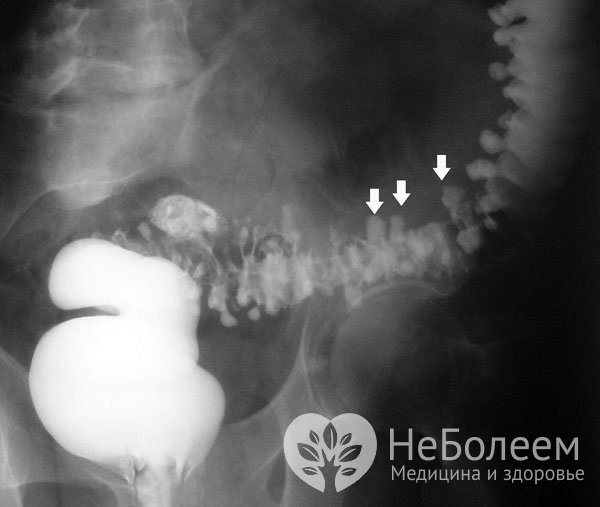

В ходе ирригоскопии наблюдают за продвижением бария на рентген-мониторе, визуализируя грыжеподобные выпячивания любой структуры, выступающие за пределы наружного контура кишки. Ирригоскопию с двойным контрастированием можно выполнять не ранее, чем через месяц-полтора после купирования острого дивертикулита.